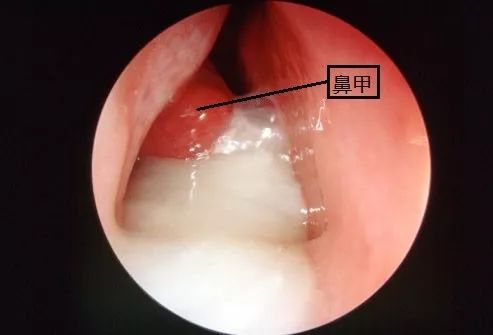

上图就是上呼吸道感染时的白色鼻涕,可以看到鼻甲是发红、肿大的,提示鼻炎。